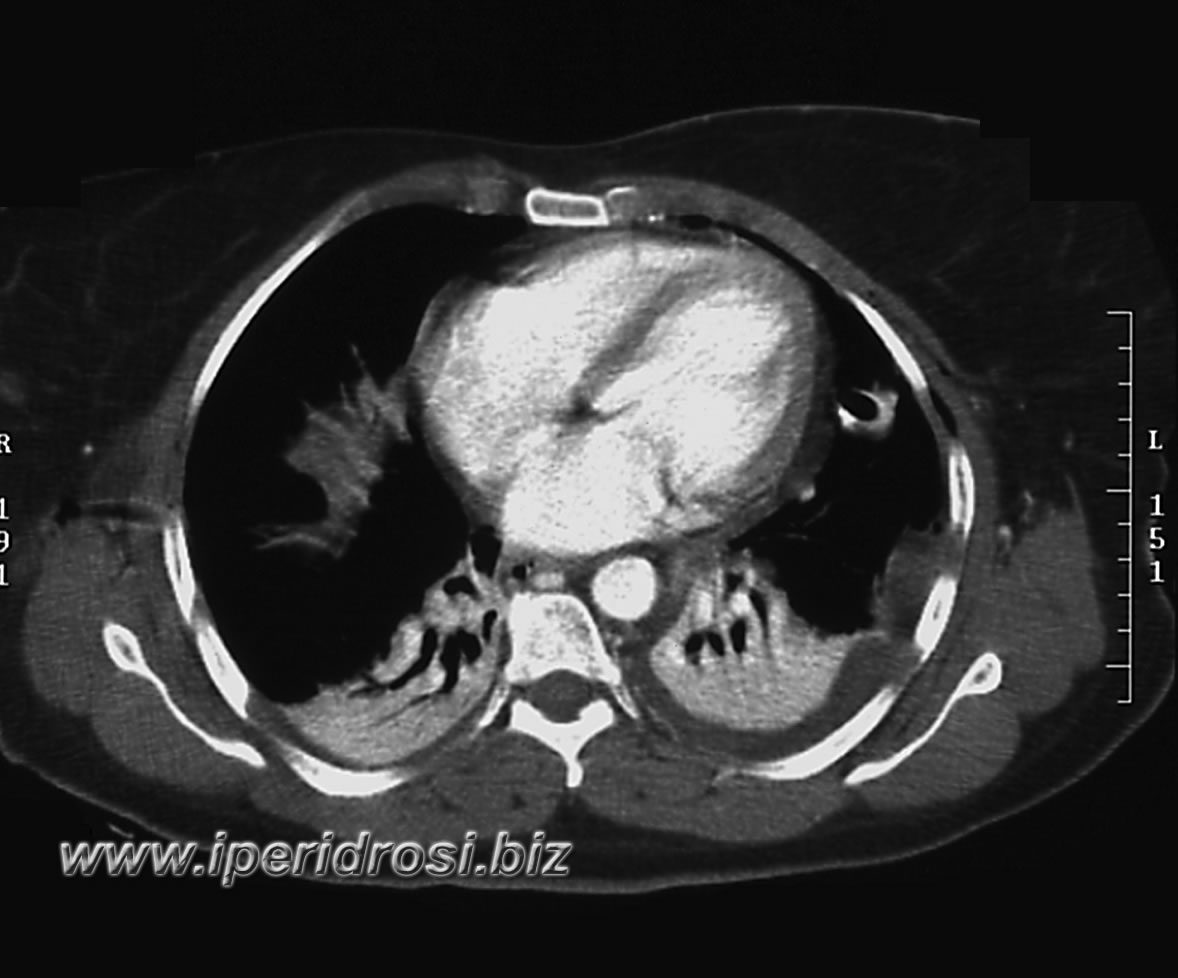

Torace: a sinistra abbondante versamento pleurico e parzialmente saccato, atelettasia parenchimale basale bilaterale più evidente a sinistra dove residua limitato parenchima ventilato.

Addome: abbondante versamento addomino-pelvico diffuso con falda aerea piuttosto abbondante all'addome superiore. Rene a ferro di cavallo con cisti parapieliche a sinistra. Distensione del colon da meteorismo ed ispessimento delle pareti intestinali con iperemia di numerose anse.